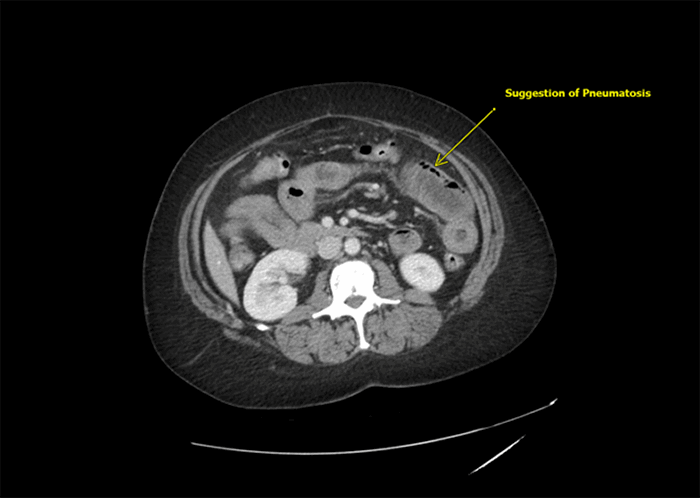

The patient is a 56-year old female with a body mass index (BMI) of 33.2 kg/m2, Type II diabetes mellitus, hypertension, asthma, and previous abdominal surgery, including appendectomy and hysterectomy. She presented to the emergency room in early May 2020 with severe periumbilical pain, rated 10/10, and nausea and vomiting, which had begun the evening prior. On physical examination, she appeared uncomfortable. She had lower and left-sided abdominal tenderness with guarding. At presentation, the patient denied fever, chills, cough, or shortness of breath. Initially, she was tachycardic (pulse rate 108) but was normotensive and had normal oxygen saturation on room air. Laboratory values were normal except for leukocytosis (white blood cell count 12.2 × 1000/μL) and elevated blood glucose. Lactate was normal at 1.1 mmol/L. Computed tomography (CT) scan showed bowel wall thickening involving large portions of the jejunum and ileum with mesenteric congestion and a moderate amount of free fluid in the pelvis (Figure 1). There was no sign of thromboembolism in the main mesenteric vessels, but there was a suggestion of pneumatosis in the left mid-abdomen (Figure 2). Peripheral patchy ground-glass opacities were seen in the visualized lower portions of both lungs, suggestive of atypical or viral pneumonia.

Figure 2. Axial CT of Abdomen and Pelvis with Intravenous Contrast; Suggestion of Pneumatosis Intestinalis. Published with Permission